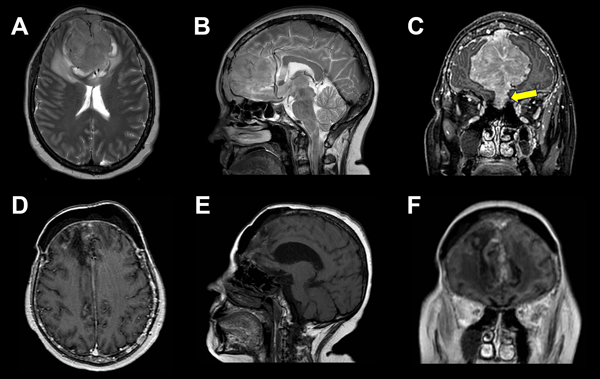

En el estudio de resonancia magnética (RM) de encéfalo se observó lesión extraaxial expansiva bifrontal con compromiso del seno frontal y tercio anterior de seno sagital superior de aspecto sólido e hipervascularizada, de aproximadamente 5.2 x 5.8 x 7.7 cm. Lesión isointensa en secuencia T1 e hipo-hiper intensa en secuencia T2, que realzaba de manera homogénea a la administración de contraste paramagnético con engrosamiento leptomeníngeo asociado. En secuencia FLAIR, se evidenció edema perilesional con colapso de las astas ventriculares frontales. En AngioRM se advirtió un gran aporte vascular de ambas arterias cerebrales anteriores, y en ventana ósea, múltiples lesiones osteolíticas en calota craneana (Figura 2).

Figura 2. A, B, C) RM preoperatoria. A) Corte axial en secuencia T2, lesión isointensa con marcado edema perilesional. B) Corte sagital en secuencia T2, arterias pericallosas desplazadas. C) Corte coronal en secuencia T1, lesión extraaxial con realce homogéneo a la administración de contraste. Invasión de los senos etmoidales (flecha amarilla). D, E, F) RM postoperatoria, en corte axial sagital y coronal se evidencia lodge de resección de LOE bifrontal sin remanente lesional y huella de craneoplastia.

Se han descripto dos patrones de extensión, la diseminación hematógena de células plasmáticas y la diseminación continua directa desde lesiones líticas erosionadas del cráneo.1,12 En cuanto al diagnóstico diferencial, destacan las similitudes imagenológicas con los meningiomas, tumores que surgen de las células aracnoideas de la duramadre y constituyen una de las neoplasias intracraneales más comunes. En RM suelen verse como una masa extraaxial redondeada de bordes suaves y circunscrita con base ancha en la superficie dural, presentan hipointensidad en secuencia T1 e hiperintensidad en secuencia T2 con realce homogéneo a la administración de contraste y el signo de “cola dural” que no es patognomónico de esta entidad y puede advertirse en otras lesiones como hemangiopericitoma, metástasis o linfomas; esto hace casi indistinguible la diferenciación preoperatoria en casos como este (ver Figuras 1 y 2).